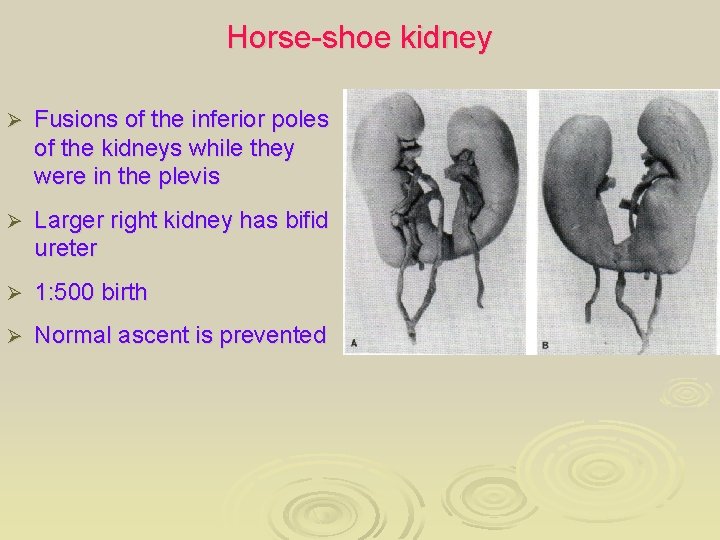

Horse-shoe kidney Ø Fusions of the inferior poles of the kidneys while they were in the plevis Ø Larger right kidney has bifid ureter Ø 1: 500 birth Ø Normal ascent is prevented